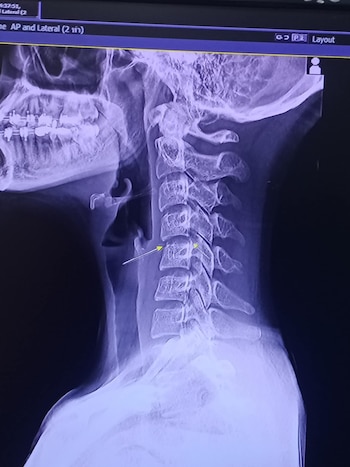

En tanto, el quiropráctico Marcelo Barroso (matrícula 9784) señaló a Infobae que “si el masaje es muy fuerte en la zona cervical es un factor a tener en cuenta porque la compresión excesiva de las caras laterales de la columna cervical y del cuello comprime las arterias que llevan y traen sangre del corazón.”

Por eso, Barroso advirtió sobre las precauciones en personas con trastornos circulatorios: “El masaje debe ser moderado en la intensidad, ya que puede alterarse el flujo circulatorio, y si tiene algún trombo y si el masaje tiene mucha intensidad, este trombo puede inclusive drenar y trasladarse hacia otros sectores con el consecuente taponamiento de la arteria o de la vena.”

“En el país hay una Asociación Argentina de Masajistas, que otorga títulos y enseña que el trabajo de la manipulación cervical y la manipulación lumbar tiene que estar hecha por especialistas y siempre con un registro previo de estudios por imágenes para evaluar si el paciente tiene, por ejemplo, algún problema arterial en el cuello o un canal cervical estrecho, que puede ser el motivo de producir una lesión grave como la que aparentemente sufrió la cantante tailandesa”, detalló el médico traumatólogo.